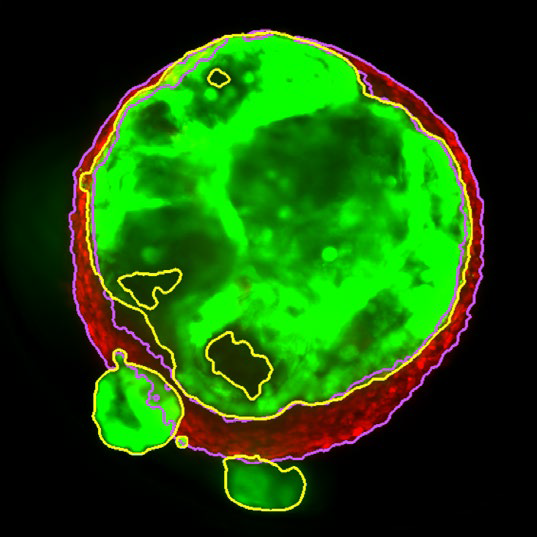

Figure 2. MaxIP image of 3D tumor co-culture microtissue - NCI-N87-GFP (gastric carcinoma; green) and NIH-RFP (murine fibroblast; red). Image Credit: Yokogawa Life Science

Tumor spheroids were created by seeding an Akura™ 384 plate with a monodispersed mixture of GFP-expressing NCI-N87 (gastric carcinoma) and RFP-expressing NIH3T3-L1 (murine fibroblast) cells, which spontaneously formed spheroids through scaffold-free self-assembly over several days. After spheroid formation, selected wells containing tumor spheroids were treated with DMSO at 0.05, 0.5, or 5.0 μM Lapatinib for six days. The images were analyzed in 3D, with NCI-N87-GFP (tumor) and NIH-RFP (fibroblast) identified separately, and the volume of each spheroid measured.